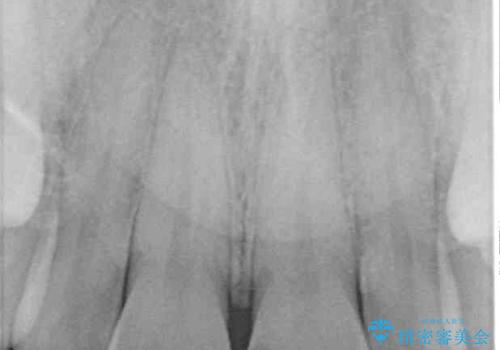

術後の経過は良好でしたが、レントゲン写真にて神経が失活している時に認められる透過像のようなものが見られました。

神経の反応はあるので失活していないようですが、時間が経過すると衝撃による失活が起こることもあるため、定期的な経過観察が必要です。